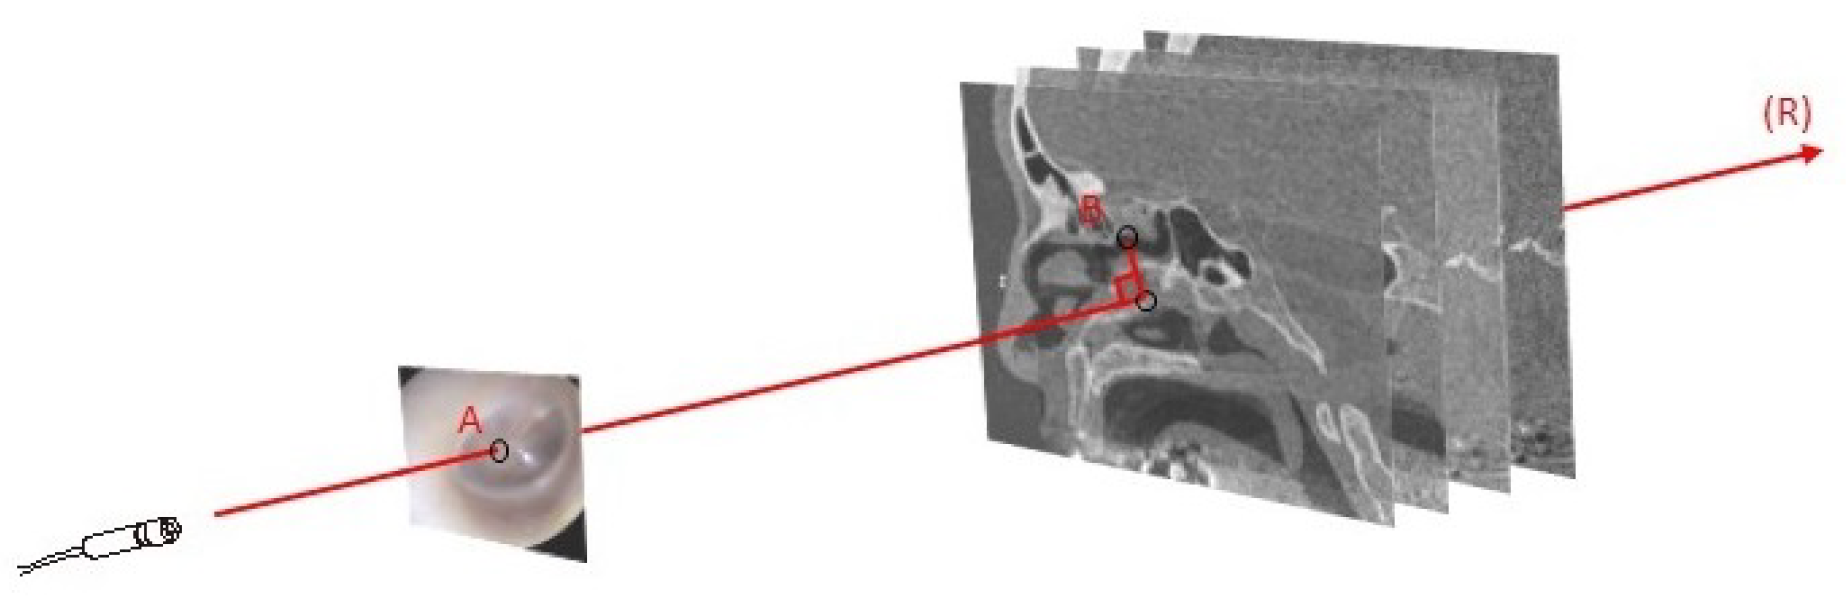

- Type of input: Preoperative images (e.g., MRI, CT scan, ultrasound (US)) provide information on the deep-seated structures and are generally acquired several hours or days before the procedure. This timing is due to the complexity of image acquisition and processing. Intraoperative imaging equipment (e.g., cone-beam computed tomography (CBCT), intraoperative CT (iCT), fluoroscopy, US, intraoperative MRI (iMRI), endoscopic cameras) or tracking devices with markers connected to the navigation system serve for the initial image-to-patient registration and also to correct navigational errors or the tissue shift during the procedure [12]. Accordingly, data could take the form of either an image or the spatial coordinates of the physical space.

- Correspondence: Establishing a correspondence between the input data is based on the input modalities and their available features. The three common approaches for determining the correspondence are [20]: segmentation [21], sparse features (i.e., points, edges, objects) [22], or signal intensity (i.e., MRI or US signal, radiological density) [23,24]. Feature-based approaches are known to be less complex in terms of computation, where the transformation matrix could be directly obtained from the correspondence of features between two modalities or by a simple algorithm (e.g., least squares [25]). Features could be physically available (fiducials) or extracted from images with image-processing techniques [26]. However, in cases where the same features are not constantly available in all situations (e.g., block of display, noisy images, anatomical deformations), the reliability becomes an issue. As an alternative, intensity approaches start from the initial default parameters, and through an optimization algorithm, the best model is selected. Here, the key relies on the selected metric, which is at the basis of integrating mutual information from both modalities [27].